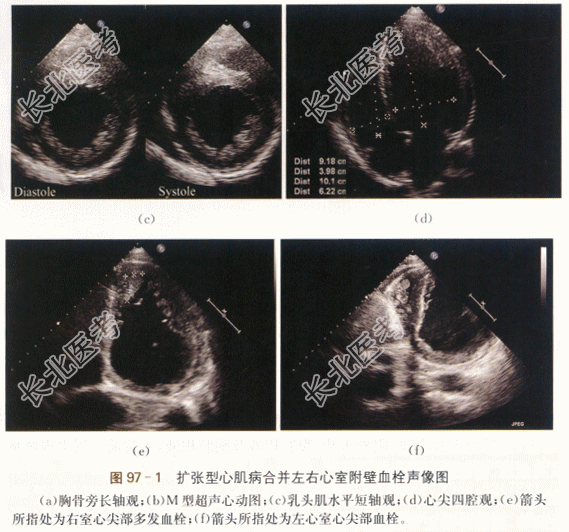

- [材料题] 患者,男性,29岁,因“双下肢水肿1周”就诊。患者1周前开始无明显诱因下出现双下肢凹陷性水肿,病情逐渐加重,先后出现双大腿、阴囊水肿、腹腔积液及胸腔积液,入院前一周出现咳嗽,夜间不能平卧。既往否认高血压、糖尿病等慢性病史。体格检查:患者慢性病容,胸廓外型正常,双侧呼吸运动对称。双肺叩诊清音,双肺呼吸音粗,双肺未及干湿啰音。心前区无异常隆起,心率80次/min,律齐,各瓣膜区未及杂音。双大腿、阴囊水肿。BNP:7958pg/ml(正常值100pg/ml),心电图ST-T改变。胸部及冠脉CT报告:全心增大、肺动脉增宽,左室侧壁及乳头肌多发密度异常,冠状动脉未见狭窄。肾穿刺提示系膜增生、IgA肾病可能。影像资料:

- 简答题1、该患者的超声诊断是什么?